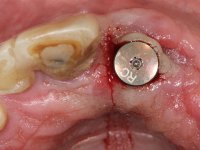

Segunda Fase

6 meses após a colocação da ponte, o paciente sofre um novo traumatismo comprometendo a viabilidade dos dentes 1.2 e 1.1. Foi realizada uma prótese removível acrílica para reabilitar provisoriamente o paciente enquanto foram extraídos os dentes 1.2 e 1.1 e foi colocado o implante no local do dente 1.1. Passados 3 meses foi realizada uma impressão ao implante colocado no 1.1 e simultaneamente foi feito um arrasto da ponte dos dentes 2.1 e 2.2. Para esse efeito no implante 2.1 foi utilizado um parafuso de uma peça de transferência. Dessa forma conseguiu-se impressionar corretamente a arquitetura gengival do sector antero-superior. O objetivo era simultaneamente impressionar corretamente esta zona e aproveitar a estrutura metálica desta ponte para confecionar a nova ponte de 4 elementos. Foi colocado um parafuso de cicatrização no implante 2.1 e foram acrescentados os dentes 2.1 e 2.2 na prótese removível. Com perícia laboratorial foi criada uma nova infraestrutura metálica de 4 elementos assente nos implantes 1.1 e 2.1 e com os elementos pônticos suspensos 1.2 e 2.2. No implante 2.1 manteve-se a conexão interna ao implante no implante 1.1 optou-se por uma peça intermédia facilitando a inserção da infraestrutura. A nova infraestrutura foi verificada em boca. Como pode ter havido alguma alteração da arquitetura gengival com a remoção da ponte e colocação do parafuso de cicatrização no 2.1, foi feita uma chave de silicone para permitir uma impressão de arrasto da infraestrutura metálica. Uma nova gengiva artificial foi realizada no modelo de trabalho de acordo com esta impressão de arrasto. Foi colocada cerâmica de tonalidade coronária e gengival. A peça protética foi aparafusada lentamente em boca para permitir uma adaptação dos tecidos moles. Após o correto assentamento e verificação imagiológica a ponte foi definitivamente apertada em boca e os orifícios de acesso obturados. Independentemente dos infortúnios que o paciente teve, pude ter a satisfação de o ver contente com esta reabilitação.